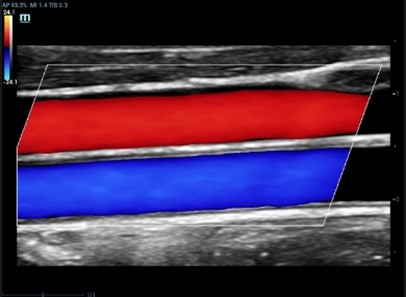

HR Flow (High Resolution Flow)

Τεχνική η οποία παρέχει αισθητά καλύτερη ποιότητα εικόνας στην PW Doppler και στην Colour Doppler απεικόνιση αυξάνοντας την ακριβή απεικόνιση των αγγείων και την ευαισθησία στην ανίχνευση της ροής αποτρέποντας την «υπερχείλιση» των αγγείων. Εφαρμόζεται σε όλες τις ηχοβόλες κεφαλές τύπου Convex, Linear, Microconvex καλύπτοντας όλο το φάσμα των διαγνωστικών εξετάσεων σε παιδιά και ενήλικες